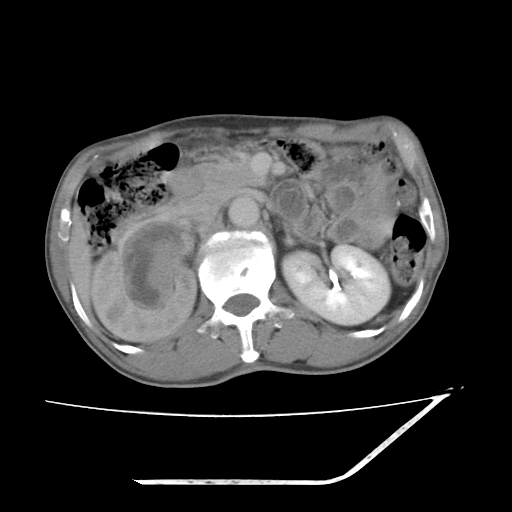

增强

考虑右肾盂癌,肾动脉受侵,右肾功能减退,右肾盂输尿管积水,管壁增厚,考虑种植转移,应该把下面扫完的

支持右侧肾盂癌伴肾静脉瘤栓形成可能性大,右肾结石.肝右叶后段低密度影,不除外转移.

右肾盂旁ca并肾静脉瘤栓形成/肾功能降低。

右肾结石。

支持 右侧肾盂癌伴肾静脉瘤栓形成可能性大,右肾结石;肝右叶后段低密度影,不除外转移。

1.右侧肾盂癌伴肾盂积水。

2.肾脏功能减退,原因有:(1)肾动脉受侵。(2)肾静脉受侵(3)肾积水,等。本例,肾动脉显影较好,但受压明显;肾静脉无明显显示,受压或静脉癌栓,下腔静脉腔内未见明显充盈缺损。

3.右侧上段输尿管扩张,原因:(1)积水所致;(2)种植。